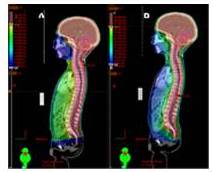

Para el tratamiento de lesiones en cráneo eje (méduloblastoma, pineoblastomas, etc.) la RAVM es la modalidad de elección primaria porque su uso disminuye la dosis recibida en estructuras como corazón, hígado, asas intestinales, etc. Se usan arcos axiales (camilla en 0°) con ángulos de inicio y finalización de 150° y 210° (paciente en posición supina) usando varios isocentros dependiendo del tamaño del paciente. En la Figura 7 se observa la distribución porcentual de la dosis en plano sagital del plan de tratamiento de un méduloblastoma usando RTC3D (Figura 7A) y usando RAVM (Figura 7B). Se observa que en este plano las estructuras anteriores torácicas y abdominales reciben considerablemente mayor dosis usando RTC3D que usando RAVM. Para este tipo de tratamientos, al compararse con RTC3D, no se obtienen grandes ventajas en lo que se refiere tiempo total de tratamiento debido a que con RAVM es mucho mayor (7,8).